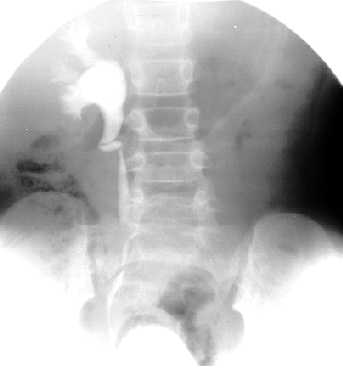

Niña de 8 años con historia de infecciones urinarias de repetición secundarias a un reflujo vesico-ureteral de grado IV.